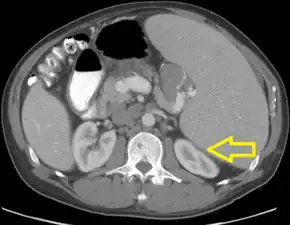

.jpg.webp)

TLS should be suspected in patients with large tumor burden who develop acute kidney failure along with hyperuricemia (> 15 mg/dL) or hyperphosphatemia (> 8 mg/dL). (Most other acute kidney failure occurs with uric acid < 12 mg/dL and phosphate < 6 mg/dL). Acute uric acid nephropathy is associated with little or no urine output. The urinalysis may show uric acid crystals or amorphous urates. The hypersecretion of uric acid can be detected with a high urine uric acid - creatinine ratio > 1.0, compared to a value of 0.6–0.7 for most other causes of acute kidney failure.